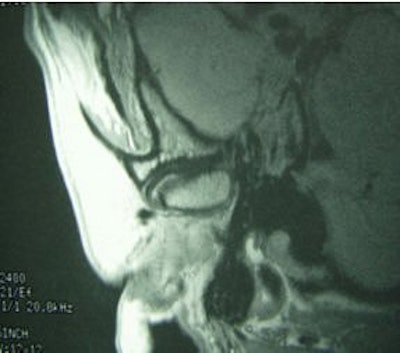

![]() |

Same patient. Postop lateral displacement of right disk. Pain improved in both joints; clicking resolved in left joint only. Images courtesy of Dr. Jessica Lee.